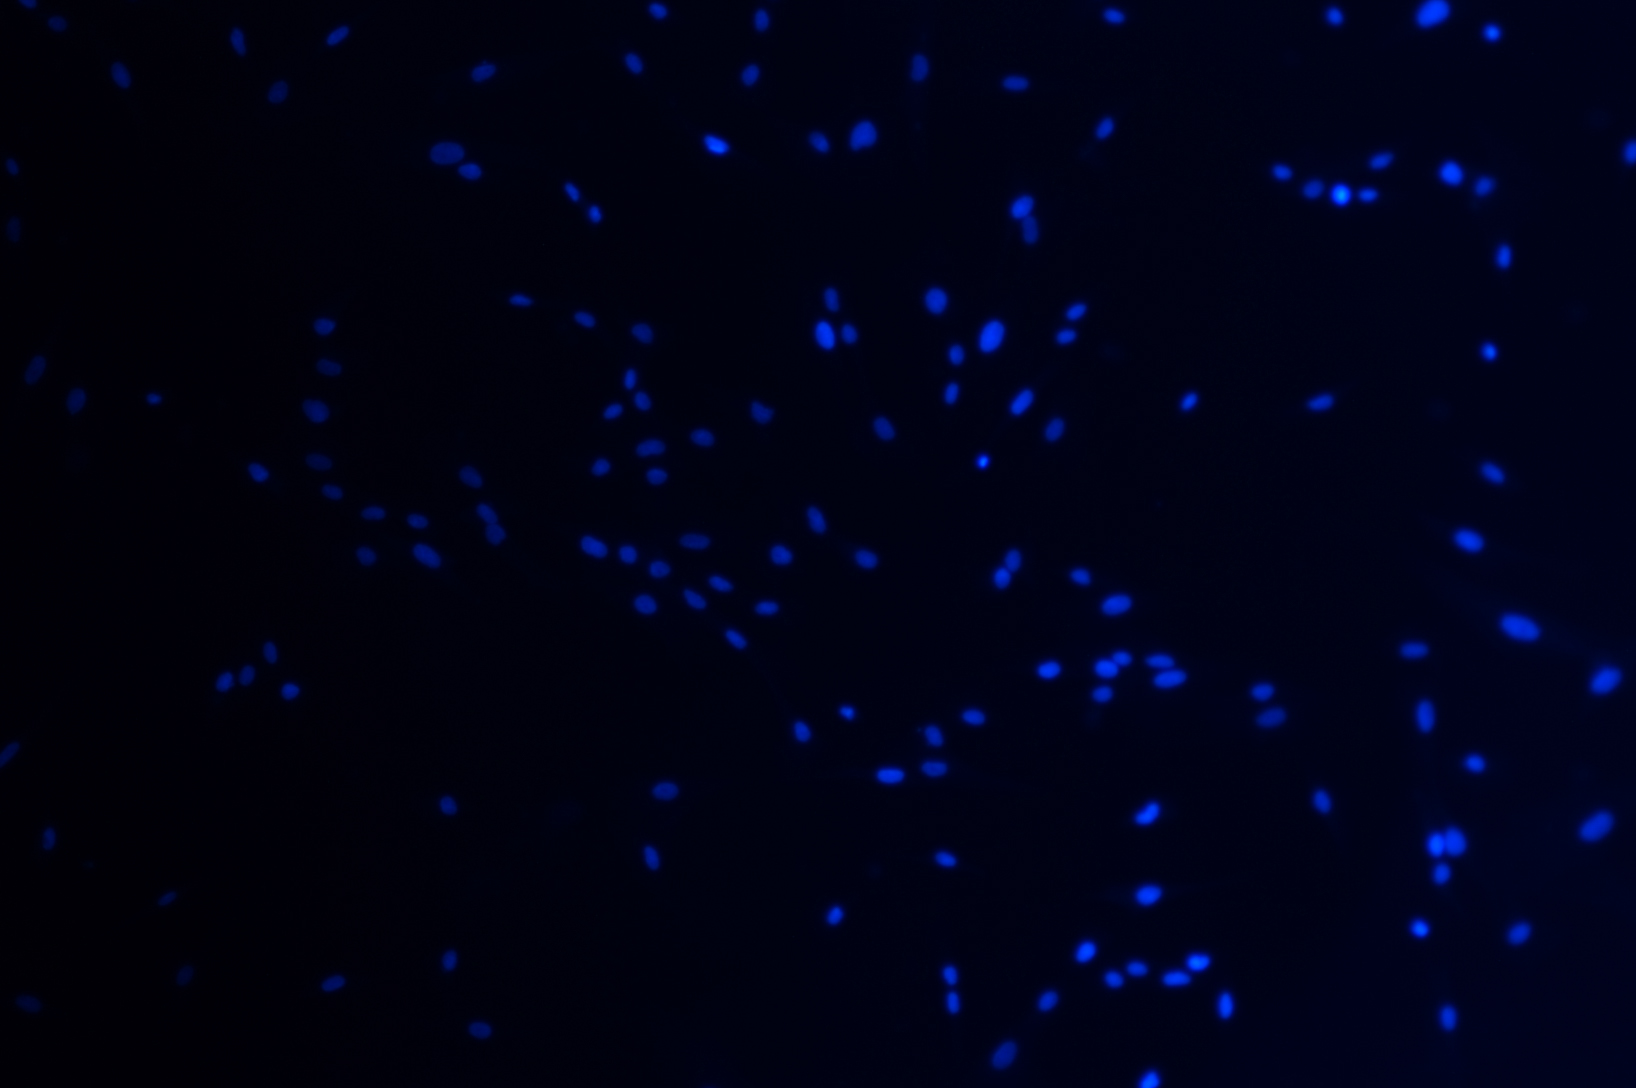

人皮膚成纖維細胞(HSF細胞)

1 來源:人皮膚

2 形態:成纖維細胞樣,貼壁生長